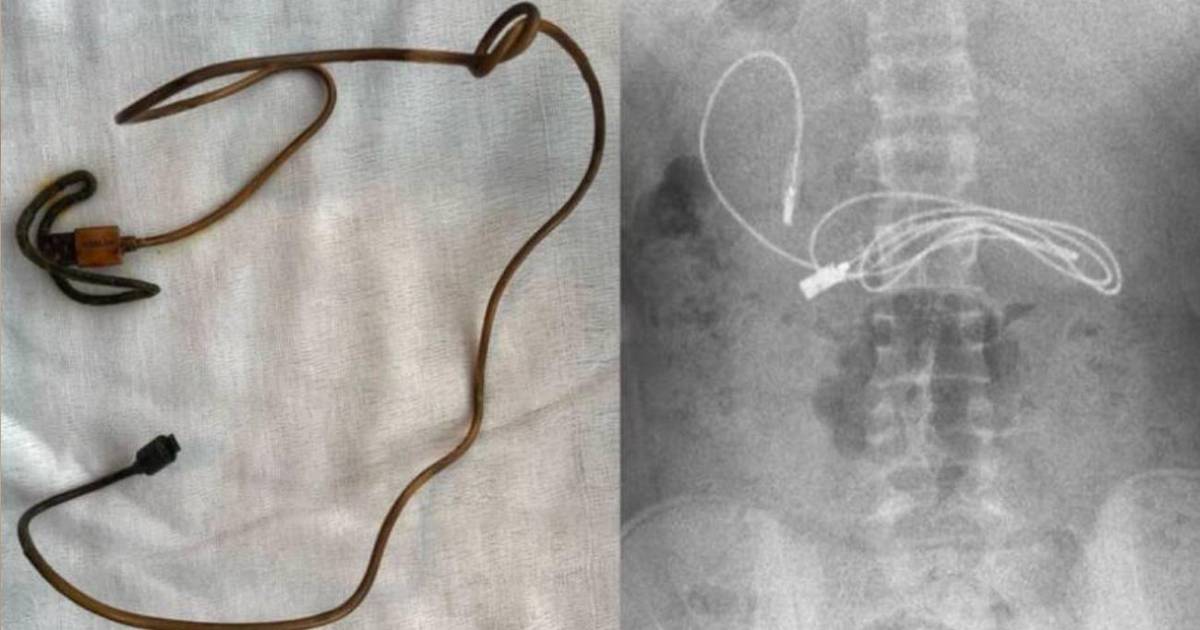

Los profesionales realizaron una serie de exámenes y se percataron de la presencia del cable y además una liga elástica para cabello en su interior. El joven tuvo que ser intervenido quirúrgicamente de emergencia.

Tuvimos dificultades para quitar el cable, ya que un extremo había pasado al intestino delgado”, dijo Yasar Dogan, gastroenterólogo que recurrió a una endoscopía a través de la boca para extraer los objetos.